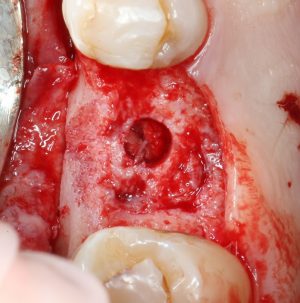

Далее, мы проходим лунку на всю глубину пилотной фрезой диаметром 2.0 мм.

После этого можно поставить пин и проверить направление и ангуляцию оси будущего имплантата.

Кстати, о пинах. В Astra Tech они, сцуко, хитрые. Диаметр тонкого конца 2.0 мм, а толстого — 3.2 мм. Это значит, что измерить и оценить ось имплантата мы можем на этапе пилотной фрезы (2.0 мм) и следующей за ней «зеленой» (3.2 мм). Далее точные изменения становятся невозможными. Платформа-ограничитель имеет размеры 3.5 (по узкой) и 5.0 (по широкой частям) мм, что позволяет оценить положение будущей лунки относительно других имплантов и соседних зубов в окклюзионной плоскости.

Следующей мы используем фрезу 2.0/3.2:

Такие фрезы — особенность имплантационной системы Astra Tech. Они нужны для того, чтобы не разломать края лунки и сделать переход между фрезами (а мы переходим с 2.0 на 3.2 мм) более точным и плавным, благодаря направляющей 2.0 мм. Однако, пройти лунку такой фрезой на всю глубину удаётся далеко не всегда. В таких случаях используется обычная спиральная фреза диаметром 3.2 мм (с зеленой полоской). Но в нашем случае такой необходимости нет, ибо выше только субантральное пространство, поэтому мы работаем только вот такой двойной фрезой.

После этого можно еще раз (последний, кстати), проверить направление и ангуляцию оси будущего имплантата. Всё тем же вышеозначенным пином: